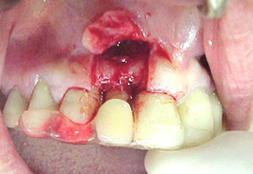

Este paciente sobre uma queda, com fratura da tábua óssea vestibular e a perda dos dentes 11, 12 e 13.

Na fotografia 1.1. Perceber-se um hematoma seguido de uma fibrose da área labial. Na fotografia 1.2. Pode-se observar a área anodôntica correspondente aos dentes e osso perdido 21 dias após o acidente.

Fotografia 1.3. Nesta fotografia, o retalho total da mucosa gengival foi rebatido, expondo o tecido ósseo. Pode-se observar a perda do cortical ósseo vestibular de toda a área. Optou-se por um enxerto de osso autógeno.

Fotografia 1.4. Observa-se o enxerto ósseo sendo removido da região mentoniana para ser colocado na área da perda óssea.

Fotografia 1.5, podemos observar, o enxerto ósseo parafusado em posição. É importantíssimo que o enxerto fique firmemente preso ao osso subjacente.